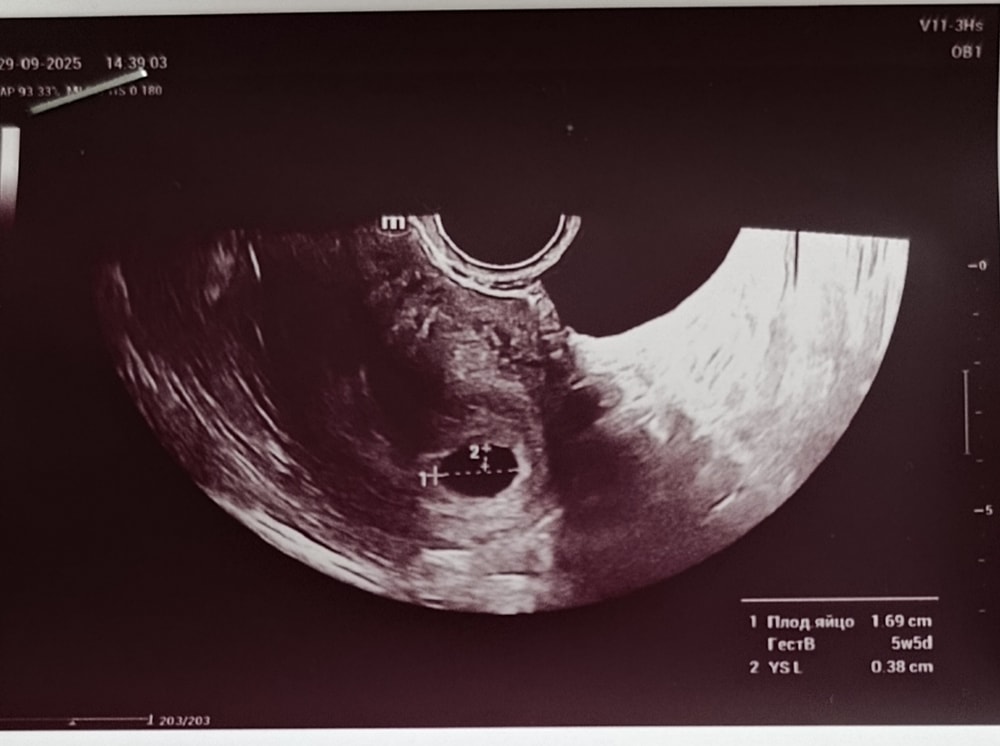

6 недель 🤰💕

Не выдержала я и все же сходила вчера на узи 😁 Беременность маточная, сроку соответствует 🙏 Эмбриона пока не видно, для сб соответственно тоже рано.